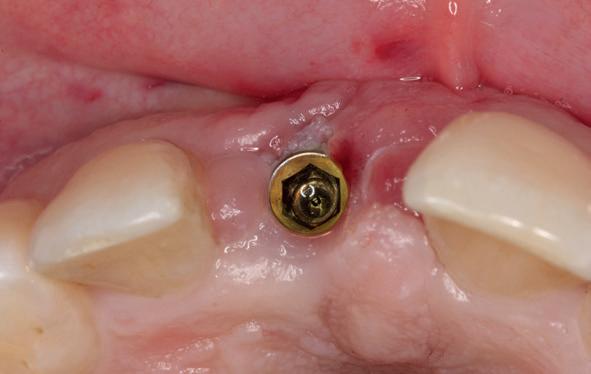

Implantologische behandelingen in het esthetische front vragen meer dan technische vaardigheid alleen. Ze vragen om overzicht, timing, vertrouwen en een team dat als vanzelf samenwerkt onder druk. Juist bij complexe casussen, waarin angst, infectie en hoge esthetische verwachtingen samenkomen, wordt zichtbaar hoe bepalend de rol van de tandartsassistent is.

Deze casus beschrijft een uitgebreide immediate implantaatbehandeling bij een patiënt die door meerdere collega’s werd geweigerd. Niet omdat de mogelijkheden ontbraken, maar omdat de complexiteit vroeg om een perfect afgestemde samenwerking. Het verhaal laat zien hoe de assistent in zo’n traject veel meer is dan een uitvoerende kracht of “mal”, maar een dynamische surgical guide die het proces mede stuurt, bewaakt en mogelijk maakt.De patiënt: wanneer alles samenkomt

De basis van een complexe beslissing

Mijn behandelplan begint altijd met een uitgebreid klinisch onderzoek. Dat omvat een medische anamnese, intra- en extra-orale camerafoto’s en uitgebreid verwachtingsmanagement. In deze fase is mijn assistent vooral bezig met het zorgvuldig vastleggen van alle gegevens. Juist dat nauwkeurig documenteren zorgt voor rust in de behandelkamer. Minstens zo belangrijk is het luisteren naar de patiënt. Niet alleen naar de klachten, maar naar het

Na het klinische onderzoek volgde het röntgenologisch traject. De CBCT liet precies zien wat we al vreesden: een front waarin het bot onregelmatig was, duidelijke radiolucenties rond de pijlers en een infectiegebied dat zich onder vrijwel de gehele brug had verspreid. Tegelijkertijd was er ook potentie. Net voldoende botstructuur om immediate implantaatplaatsing te overwegen, mits alles perfect gepland zou worden.